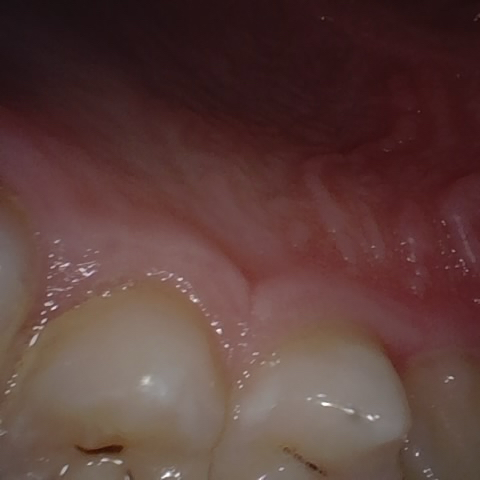

Annotated as "Good"